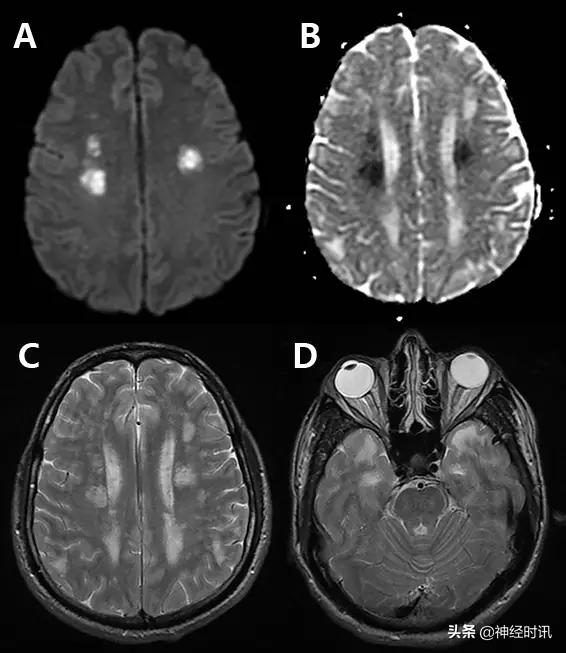

图4 一例72岁男性,精神状态改变,右下肢局灶性运动性癫痫持续状态,同时存在发热伴分泌性咳嗽。该患者最初被诊断为双侧ACA和MCA脑梗死。最后患者被诊断为HSV脑炎,MRI显示双侧颞叶、额叶、岛叶、扣带回和丘脑非对称性多灶性弥散受限(A-D,DWI)、T2/FLAIR高信号(图像未提供)。

图5 一例51岁女性,表现为意识不清,言语含糊,近事遗忘。发病后4天DWI显示双侧海马点状弥散受限(A&B:DWI;C&D:ADC)。随访MRI显示病灶完全缓解(图像未提供)。

图6 一例48岁男性,近期2次左侧PCA分布区梗死,伴神经功能缺损加重,新发认知功能障碍和意识障碍。最终诊断为MELAS,FLAIR显示左侧后顶颞针叶非血管性分布的皮层水肿(A:FLAIR),同时伴弥散受限和弥散增加(B:DWI;C:ADC)。